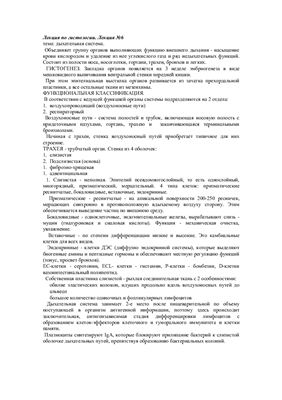

Дыхательные пути представляют собой систему трубок, просвет которых формируется благодаря наличию в них костей и хрящей . Внутренняя поверхность дыхательных путей …

Дыхательнаясистемачеловекасостоитизтканейиорганов,обеспечивающихлегочную вентиляциюилегочноедыхание .К воздухоносным путям относятся: нос, полость носа, носоглотка, …

Дыхательная система (дыхательный аппарат), systema resperatorium, состоит из дыхательных путей и парных дыхательных органов - легких . Дыхательные пути …

Дыхательная система . Дыхание как совокупность процессов, обеспечивающих поступление в организм кислорода и удаление углекислого газа . Органы, входящие в состав верхних …

Основной механизм регулирования дыхания — центральная нервная система . Дыхательный центр регулирует частоту и ритм дыхания .